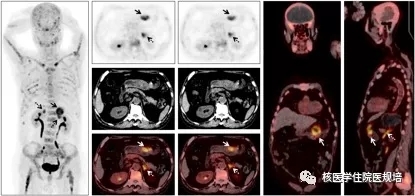

为进一步准确分期,该患者于骨显像后进行了68Ga-PSMA PET/CT显像(图2)。结果示:中轴骨及四肢骨呈68Ga-PSMA弥漫性高摄取;骨盆多骨呈成骨性骨质破坏改变伴68Ga-PSMA弥漫性摄取升高(SUVmax:3.45);余全身淋巴结及内脏器官未见68Ga-PSMA异常摄取及异常结构改变。符合前列腺癌多发骨转移。

图2 68Ga-PSMA PET/CT全身MIP图及横断位PET、CT、融合图

该患者随后行PET/CT引导下穿刺活检,选择右侧髂骨PSMA摄取增高灶作为活检靶区(图2箭头),但*终病理诊断考虑转移性腺癌,免疫组化结果CK7阳性、NKX3.1阴性不支持前列腺癌转移,建议查找消化道等其他器官是否有原发灶。临床医师为进一步明确该恶性病变的原发灶,在患者及其家属知情同意的情况下,该患者入组我院68Ga-FAPI PET/CT显像的临床试验(图3)。

图3 68Ga-FAPI PET/CT全身MIP图及横断位PET、CT、融合图

追加的68Ga-FAPI PET/CT显像

68Ga-FAPI PET/CT显像示:中轴骨及四肢骨多发68Ga-FAPI异常浓聚灶。腹部区域可以观察到三个异常浓聚灶(箭头)。腹部横断位图像示:胃窦部胃壁(实箭头)稍增厚伴68Ga-FAPI局灶性摄取升高;双侧肾上腺(虚线箭头)68Ga-FAPI摄取升高,同机CT未见明确形态学改变。显像结果提示:胃窦部恶性肿瘤伴全身广泛骨转移;双侧肾上腺FAPI高摄取病灶考虑为激素治疗引起的慢性炎症所致。